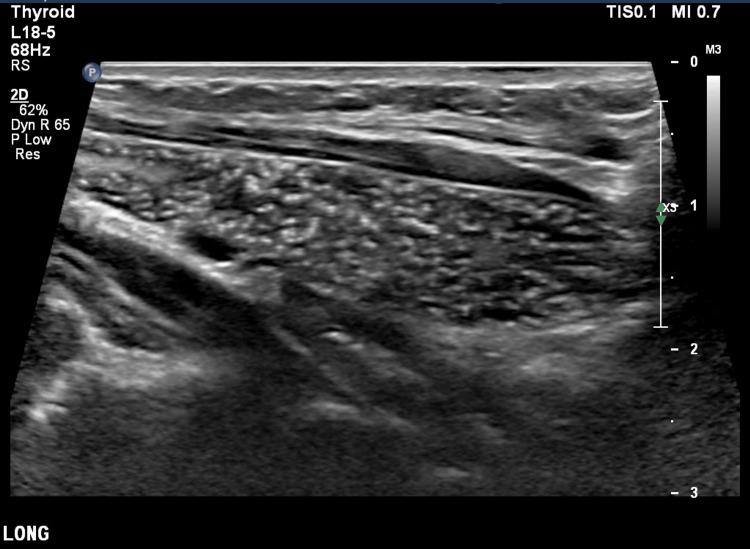

We present a case of conservatively managed intrathyroidal thymic tissue in a 3.5-year-old girl, who had an ultrasound for a midline swelling that was consistent with a dermoid cyst, proven by operative specimen pathology. An incidental finding was that of thymic tissue within the thyroid, the ultrasound characteristics of which enable differentiation from thyroid malignancy, enabling a confident diagnosis of this benign, asymptomatic condition. Thus, rather than proceeding to invasive investigations, detailed ultrasound analysis obviates the need for thyroid biopsy. The features that enable malignancy to be excluded are discussed.

我们报告一例3.5岁女孩的甲状腺内胸腺组织保守治疗病例。该女孩因中线肿胀接受超声检查,最初诊断为皮样囊肿,手术标本病理证实。偶然发现甲状腺内存在胸腺组织,其超声特征有助于与甲状腺恶性肿瘤相鉴别,从而确诊这种良性、无症状的情况。因此,无需进行侵入性检查,详细的超声分析避免了甲状腺活检的必要性。文中讨论了能够排除恶性肿瘤的特征。